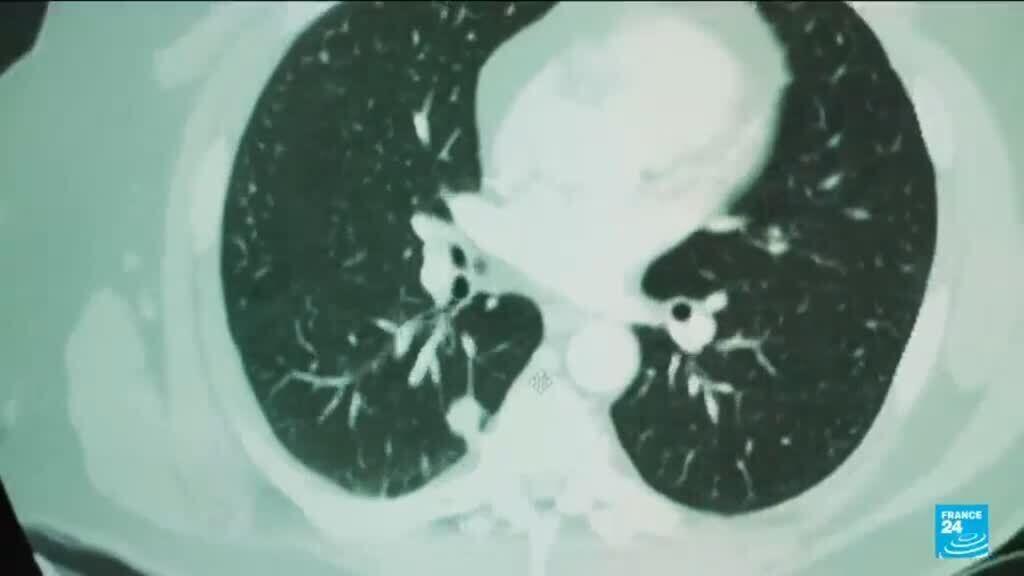

On World Cancer Day, attention is turning to a world-first trial showing that artificial intelligence is helping doctors identify more cases of breast cancer during routine screenings. Researchers in Sweden say the results could lead to wider use of AI to ease the workload of radiologists, while emphasising that the technology is designed to support clinicians rather than replace them. Charlotte Lam and Elliot Samuel have more.